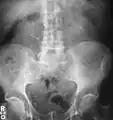

Calcium-containing stones are relatively radiodense (opaque to X-rays), and they can often be detected by a traditional radiography of the abdomen that includes the kidneys, ureters, and bladder (KUB film).[59] KUB radiography, although useful in monitoring size of stone or passage of stone in stone formers, might not be useful in the acute setting due to low sensitivity.[60] Some 60% of all renal stones are radiopaque.[61][62] In general, calcium phosphate stones have the greatest density, followed by calcium oxalate and magnesium ammonium phosphate stones. Cystine calculi are only faintly radiodense, while uric acid stones are usually entirely radiolucent.[63]

Bilateral kidney stones can be seen on this KUB radiograph. There are phleboliths in the pelvis, which can be misinterpreted as bladder stones.